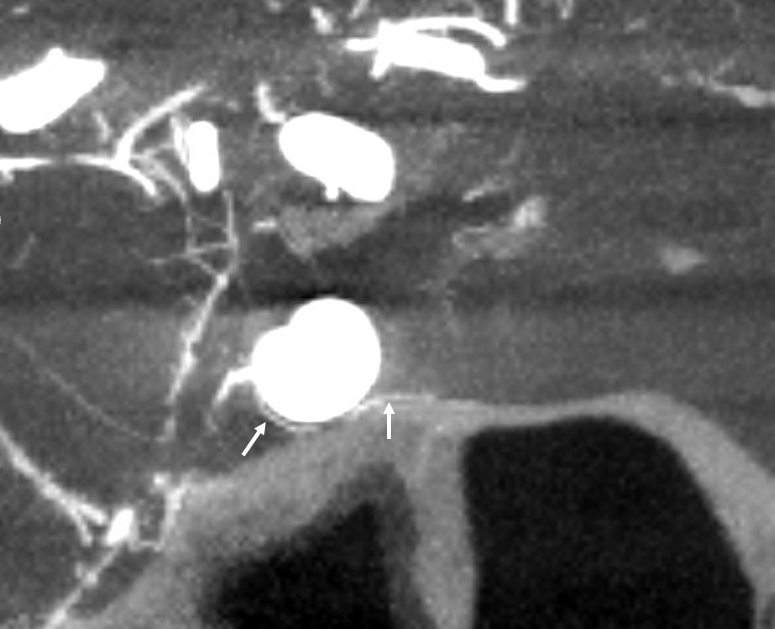

Capsular Arteries of McConnell

These are different from Superior Hypophyseals, but often come up together. This is because they were described by McConnell in a fantastic manuscript on arterial supply to the hypophysis. The anterior hypophysis is supplied by the aforementioned superior hypophyseals. Posterior by the inferior hypophyseals. The arteries of McConnell supply the dura and bone of the sella turcica. They are considered dural, and do not as a rule supply the hypophysis. Too small for even HR CBCT resolution, they are found in about 1/3 to 1/2 of surgical dissections. Origin is from the MEDIAL aspect of the horizontal cavernous segment (opposite side of ILT). Courses medially towards the bottom of the sella. Below (arrows) is a particularly large one (because it feeds some posterior pituitary for some reason). Note beautiful anterior pituitary / stalk supply on bottom right image.

Without arrows: